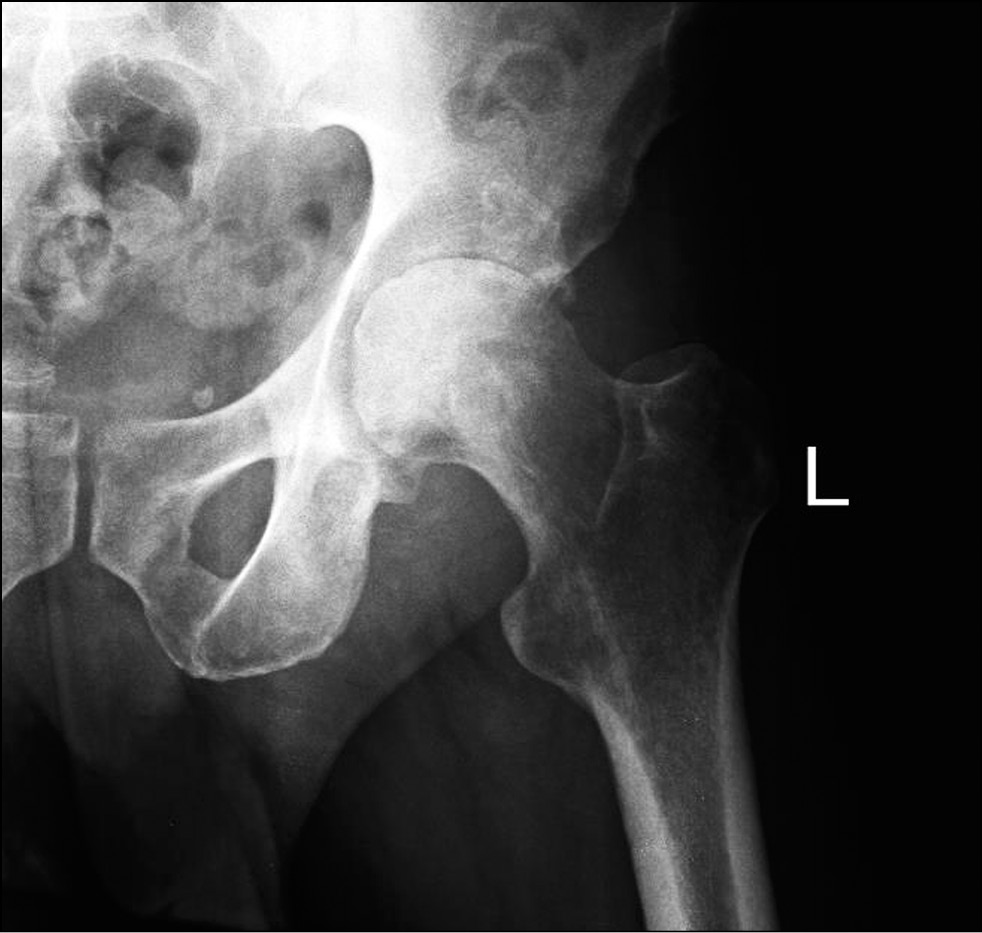

В марте 2023 года пациент был госпитализирован в хирургическое отделение № 2 клиники пропедевтической хирургии (отделение гнойной хирургии) клиник СамГМУ с подозрением на септический коксит слева, некроз головки левой бедренной кости. При поступлении уровень лейкоцитов составлял 11,3×109/л, СРБ — 97,3 мг/л, СОЭ — 24 мм/час. Дополнительные инструментальные исследования не выявили септических очагов иной локализации. При повторном проведении МРТ тазобедренных суставов были выявлены следующие изменения: резко выраженный синовит, выраженная гипертрофия суставной капсулы, отёк периартикулярных мягких тканей, не свойственные для типичной картины АНГБК (рис. 2).

Рис. 2. Предоперационная магнитно-резонансная томограмма тазобедренных суставов пациента С., 38 лет, в коронарной проекции.